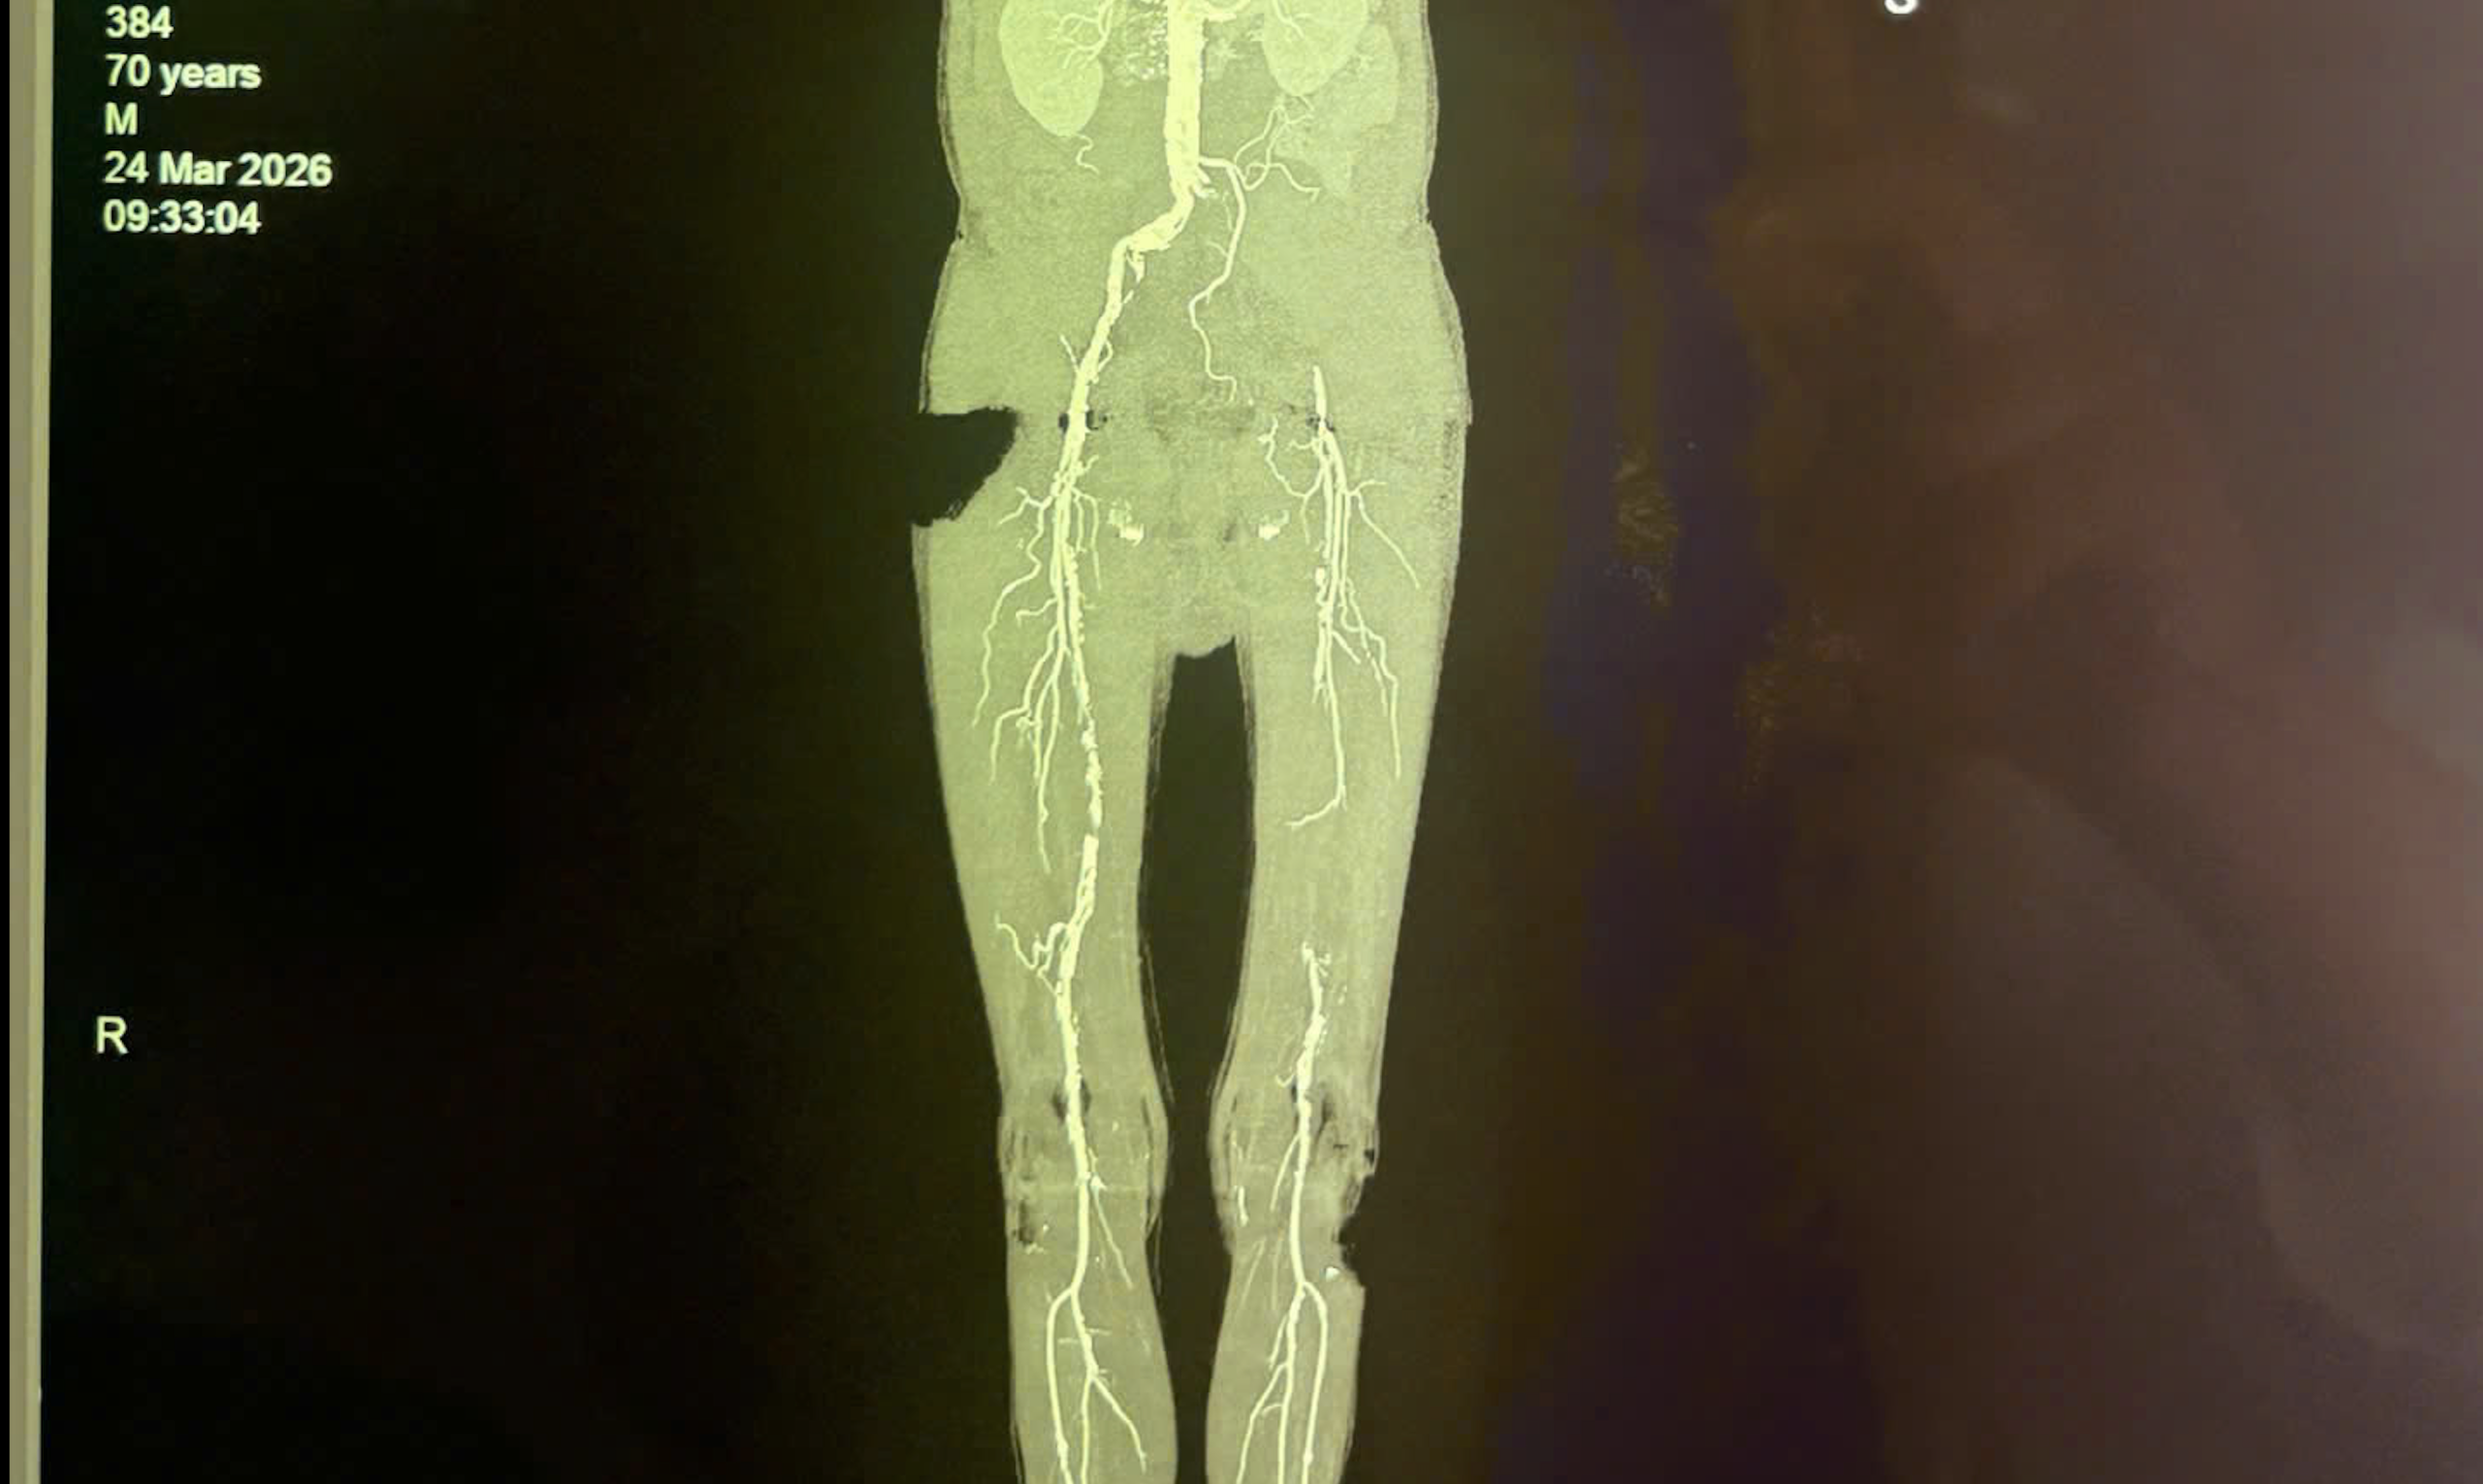

Hình ảnh chẩn mạch chi của bệnh nhân bị tắc nhiều đoạn có nguy cơ gây biến chứng hoại tử, cưa chân

Qua thăm khám lâm sàng, các bác sĩ ghi nhận động mạch đùi, động mạch khoeo và động mạch dưới gối chân bên trái của bệnh nhân không bắt được. Kết quả siêu âm Doppler mạch máu chi dưới ghi nhận tắc động mạch chậu bên trái, mất phổ 3 pha động mạch đùi, khoeo chân trái. Bệnh nhân được chụp cắt lớp vi tính mạch máu chi dưới (CTA) để đánh giá cụ thể và chính xác hơn tình trạng bệnh lý mạch máu, vị trí tắc nghẽn, mức độ tổn thương mạch máu.

Kết quả cho thấy bệnh nhân bị tắc động mạch chậu bên trái, tắc 1/3 giữa động mạch đùi bên trái và xơ vữa rải rác các động mạch chi dưới khác.